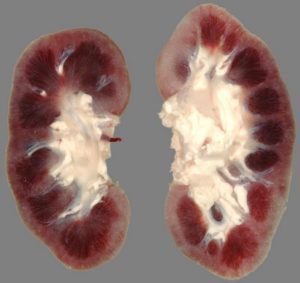

Морфологические изменения в почках

Изменения зависят от причины и типа почечной недостаточности. При острой почечной недостаточности нарушения чаще связаны с синдромом «шоковой почки» или зависят от токсических свойств ядовитого вещества.

Шоковая почка

Почечная ткань при шоковой почке имеет бледный корковый слой и полнокровие юкстамедуллярной зоны. Гистологически наблюдаются очаги пораженного эпителия канальцев с дистрофией клеток, реже — некроз.

Если шок вызван гемолизом или разрушением мышечной ткани при синдроме длительного сдавления, в почках выявляют нефрозоподобные изменения и тромбоз капилляров клубочков. Аналогичные изменения наблюдаются при:

• бактериальном шоке и сепсисе;

• синдроме диссеминированного внутрисосудистого свертывания;

• эмболии околоплодными водами, осложняющей беременность.

При затяжной почечной недостаточности характерно истончение коркового вещества. Патология беременности может сопровождаться кровоизлияниями и некрозом в корковом слое надпочечников.

Участки некроза ограничены демаркационным лейкоцитарным валом, в дальнейшем в них формируются кальциноз или фиброз.

Токсическая почка

Изменения зависят от свойств нефротоксических веществ. Под воздействием ядов, блокирующих сульфгидрильные группы (например, солей тяжелых металлов), развивается коагуляционный некроз эпителия канальцев. К концу первой недели происходит отторжение некротических масс и начинается регенерация клеток.

При отравлении этиленгликолем наблюдается симметричный некроз коркового слоя, сопровождающийся нефрозом. Почка увеличивается в размерах. Гистологически выявляются: